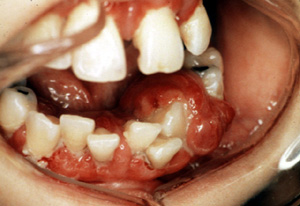

Aquí hay otro ejemplo típico ocurriendo en el mucosa edéntula. Incluso la irritación más ligera puede causar  hemorragia. Un granuloma  piógeno  pueden crecer rápidamente y pueden simular un tumor maligno; obviamente, el diagnóstico preciso requiere de la biopsia.